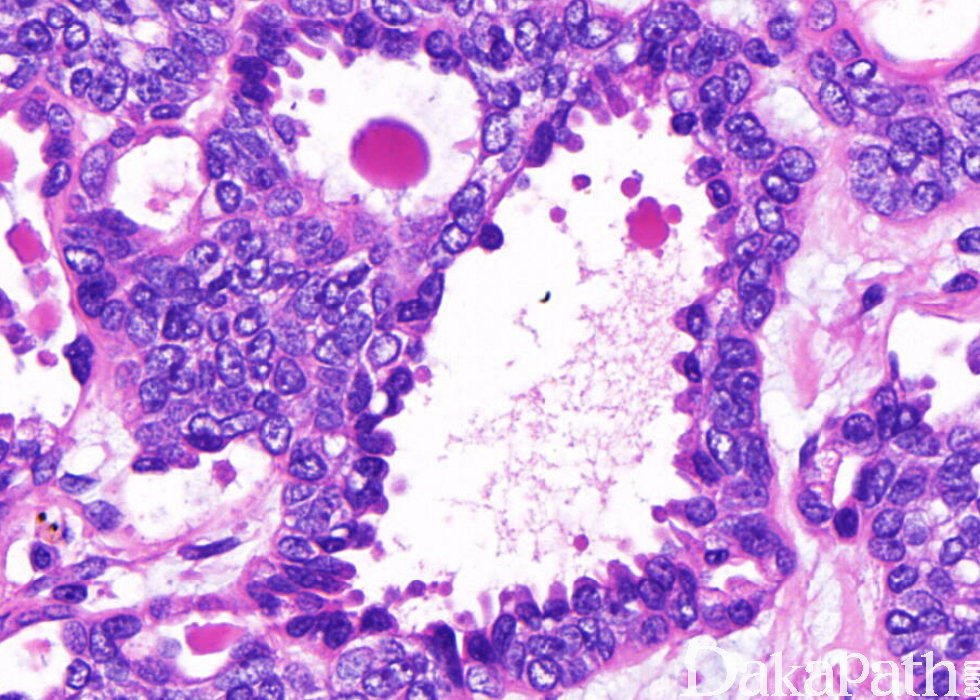

由两种细胞不同比例混合组成管状结构,偶可形成实性细胞巢;

典型的导管由双层细胞衬附,由伴有嗜酸性胞浆的立方形内层细胞和伴有明显透明胞浆的外层细胞组成;

肌上皮细胞有时呈梭形,其增生形成实性细胞巢,其间很少腺上皮,甚至完全由肌上皮组成;